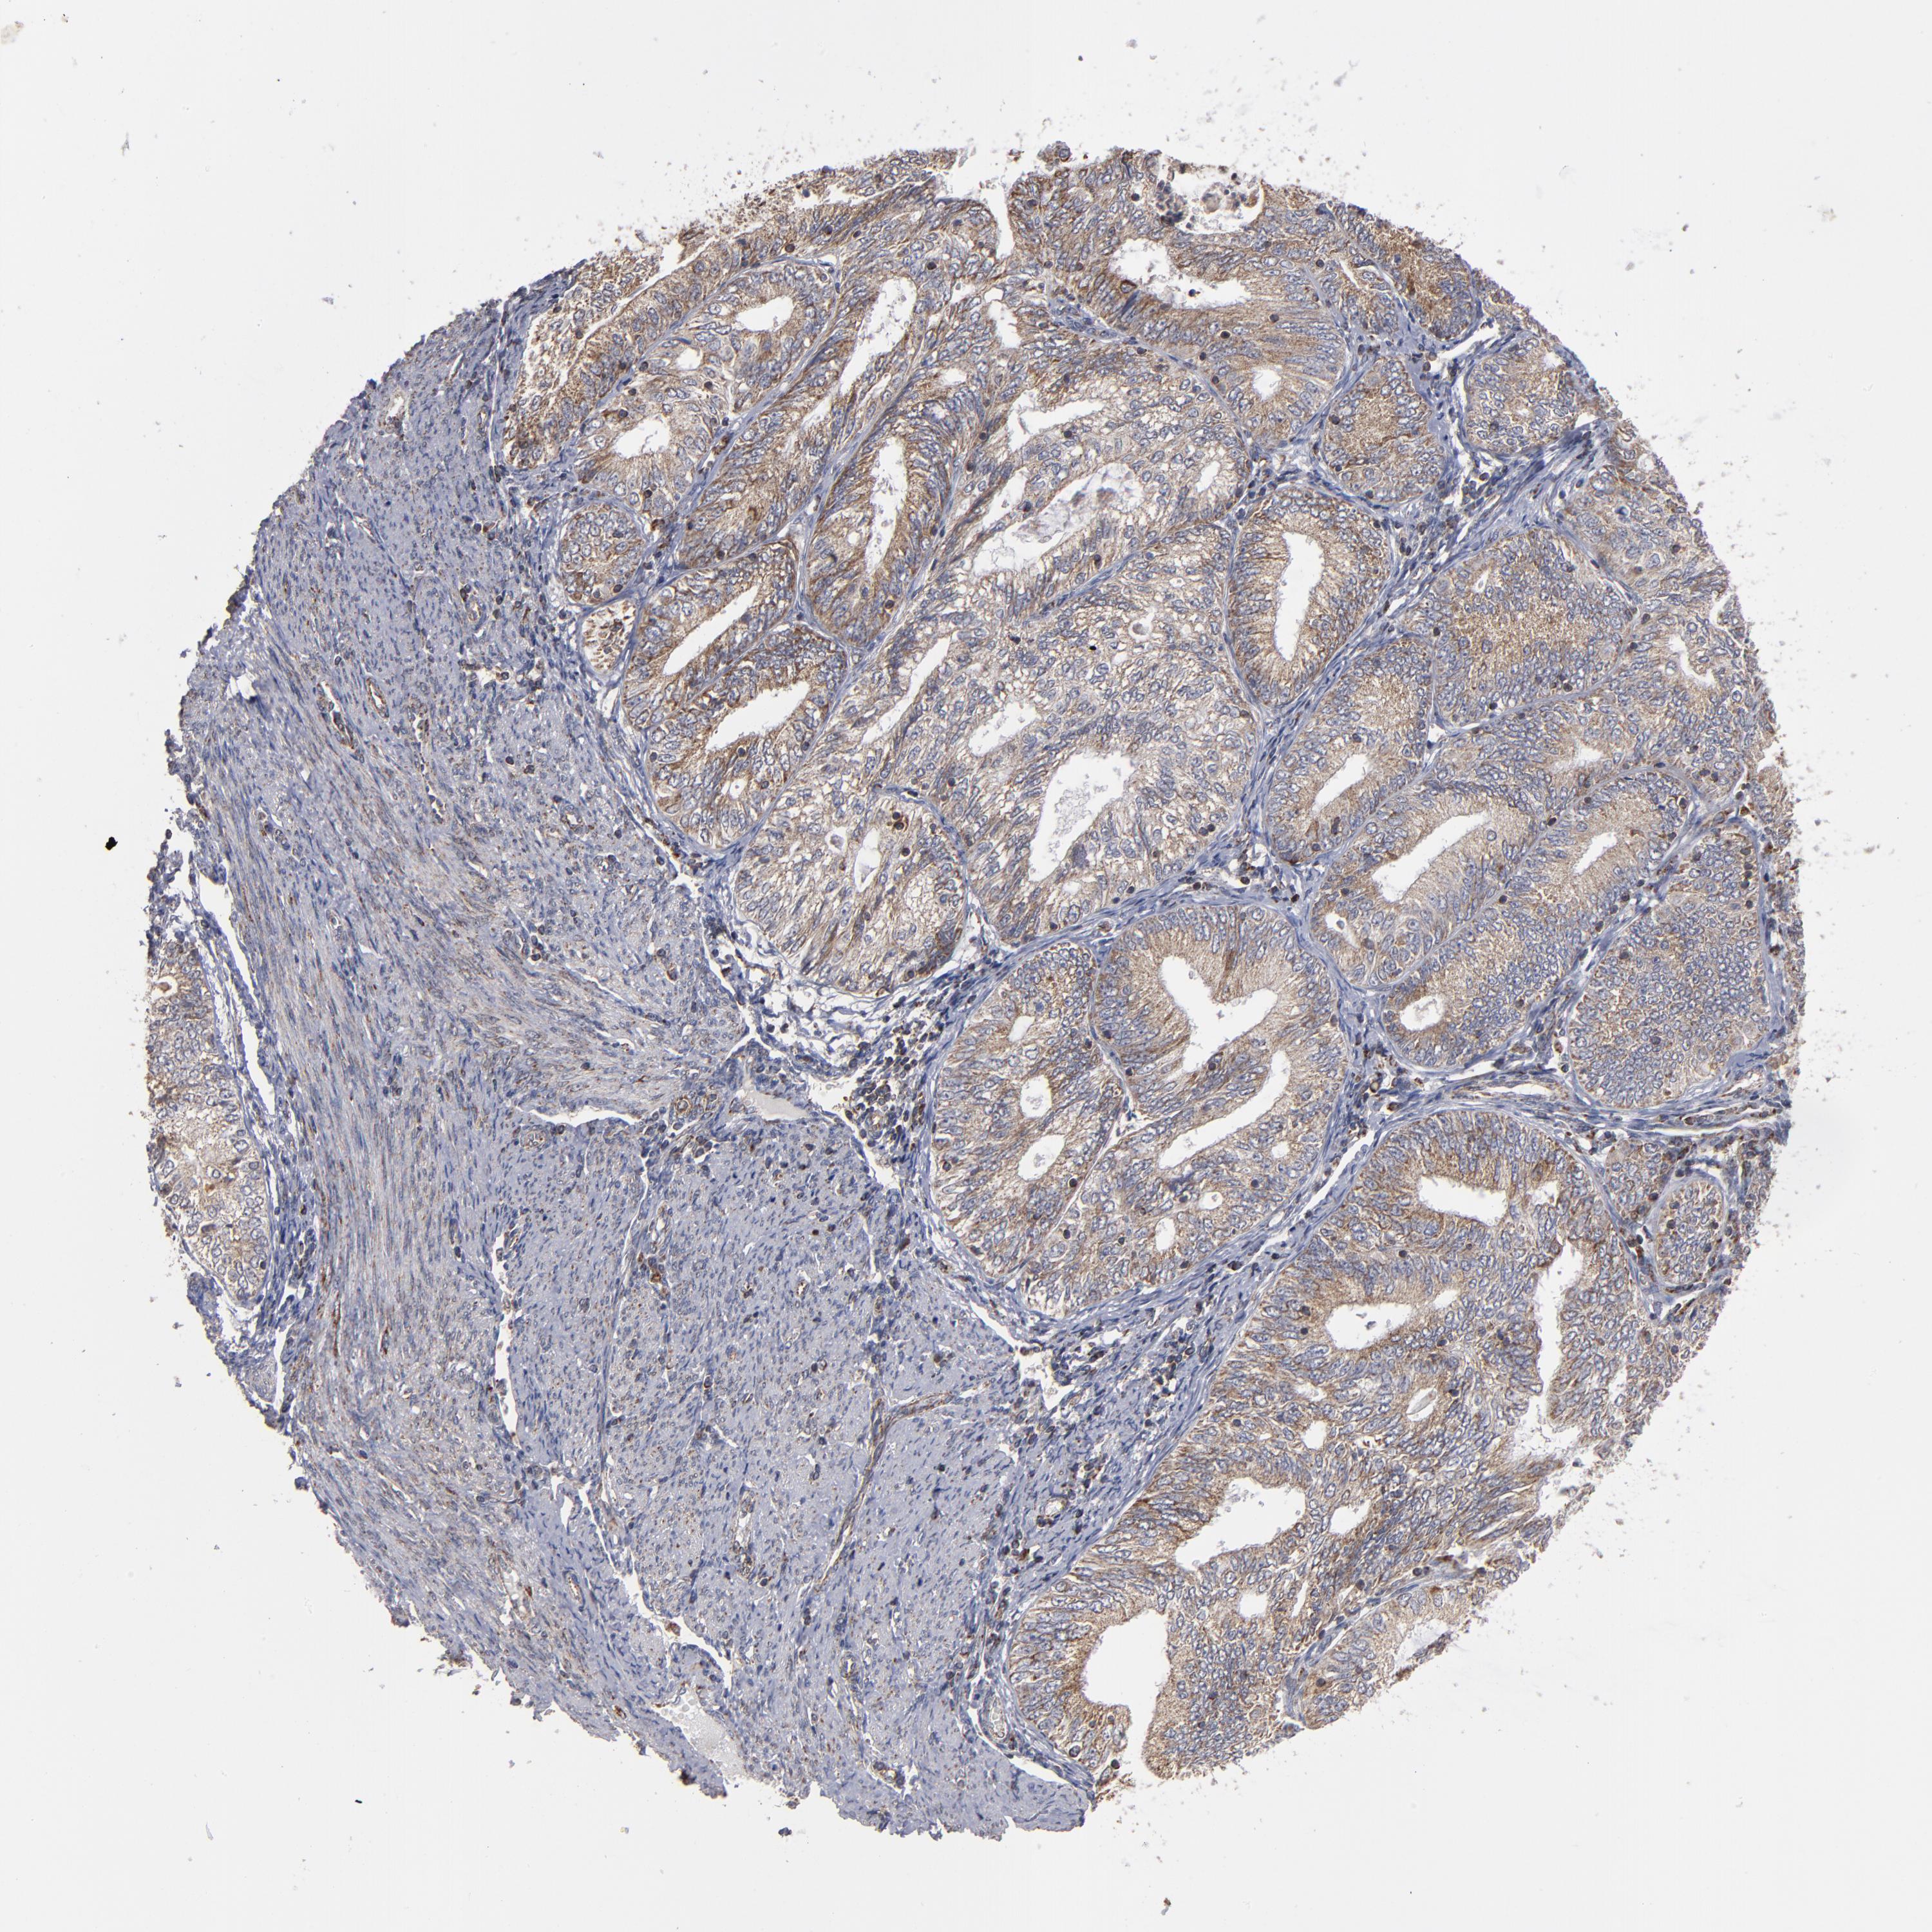

ENDOMETRIAL CANCER - Protein expressioni

A mouse-over function shows sample information and annotation data. Click on an image to view it in a full screen mode. Samples can be filtered based on level of antibody staining by selecting one or several of the following categories: high, medium, low and not detected. The assay and annotation is described here.

Note that samples used for immunohistochemistry by the Human Protein Atlas do not correspond to samples in the TCGA dataset.

Antibody stainingi

Antibody staining in the annotated cell types in the current human tissue is reported as not detected, low, medium, or high, based on conventional immunohistochemistry profiling in selected tissues. This score is based on the combination of the staining intensity and fraction of stained cells.

Each image is clickable and will lead to virtual microscopy that enables deeper exploration of all samples and also displays staining intensity scores, fraction scores and subcellular localization as well as patient and tissue information for each sample.

Antibody HPA002893

Staining

High

Medium

Low

Not detected

Intensity

Strong

Moderate

Weak

Negative

Quantity

>75%

75%-25%

<25%

None

Location

Nuclear

Cytoplasmic/membranous

Cytoplasmic/membranous,nuclear

Adenocarcinoma, NOS

Neoplasm, malignant, NOS